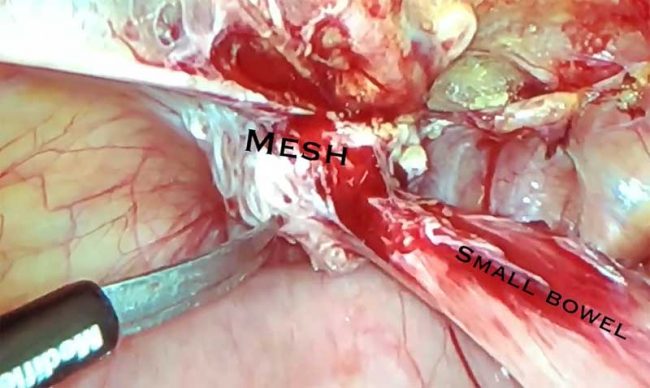

New technique for repairing Diastasis Recti

New technique for repairing Diastasis Recti by Dr. Iraniha Diastasis Recti or diastasis of Rectus muscles is a common condition when the anterior abdominal wall muscles called rectus muscles have separated from each other and weakened the core muscle strength. This condition also associated with abdominal wall bulge with abnormal body posture, lower back pain…